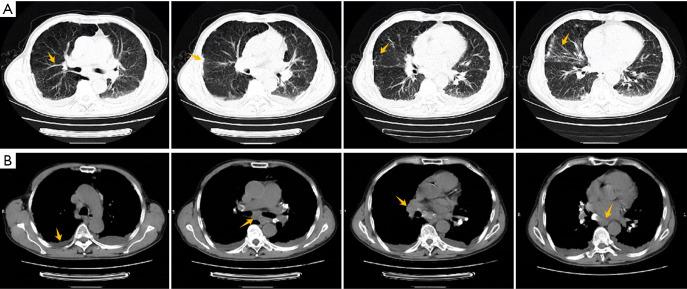

A 70-year-old man was hospitalized with cough and dyspnea for two months. After admission, through chest computed tomography (CT), ultrasound guided bilateral lung biopsy, left parietal pleural biopsy, and EBUS-CA-TBMCB, the final diagnosis was atypical sarcoidosis secondary FM. After taking glucocorticoid orally, the patient's condition improved significantly, and was discharged from the hospital. We continued following up outside the hospital, and the patient's condition was further improved.

The diagnosis of FM is mainly based on typical imaging manifestations. When the contrast-enhanced chest CT finds localized or diffuse soft tissue density shadows around the mediastinum and pulmonary hilum with an irregular shape, with or without calcification, particular attention should be paid to exclude FM. EBUS-CA-TBMCB, as an improved minimally invasive method, can obtain enough tissue samples for pathological diagnosis, which may be the effective biopsy method for the etiology of FM to avoid missed diagnosis and misdiagnosis in the future.

一名70岁男性因咳嗽、呼吸困难2个月入院。入院后,通过胸部计算机断层扫描(CT)、超声引导下双侧肺活检、左顶叶胸膜活检及EBUS-CA-TBMCB,最终诊断为非典型结节病继发FM。口服糖皮质激素后,患者病情明显改善,出院。我们继续在院外随访,患者病情进一步好转。

结论

FM的诊断主要基于典型的影像学表现。当胸部增强CT发现纵隔和肺门周围有局部或弥漫性软组织密度影,形态不规则,有无钙化时,应特别注意排除FM。EBUS-CA-TBMCB作为一种改良的微创方法,能够获取足够的组织样本进行病理诊断,可能是避免未来FM病因漏诊和误诊的有效活检方法。